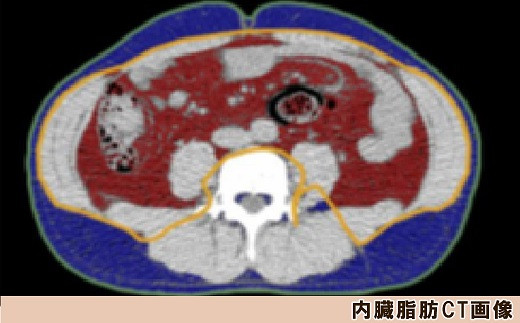

◆内臓脂肪CT検査

動脈硬化進行に関係する内臓脂肪量、内臓脂肪型肥満かどうかを調べる検査です。おへそのレベルでお腹の断層画像をCTで撮影して内臓脂肪面積を計測します。